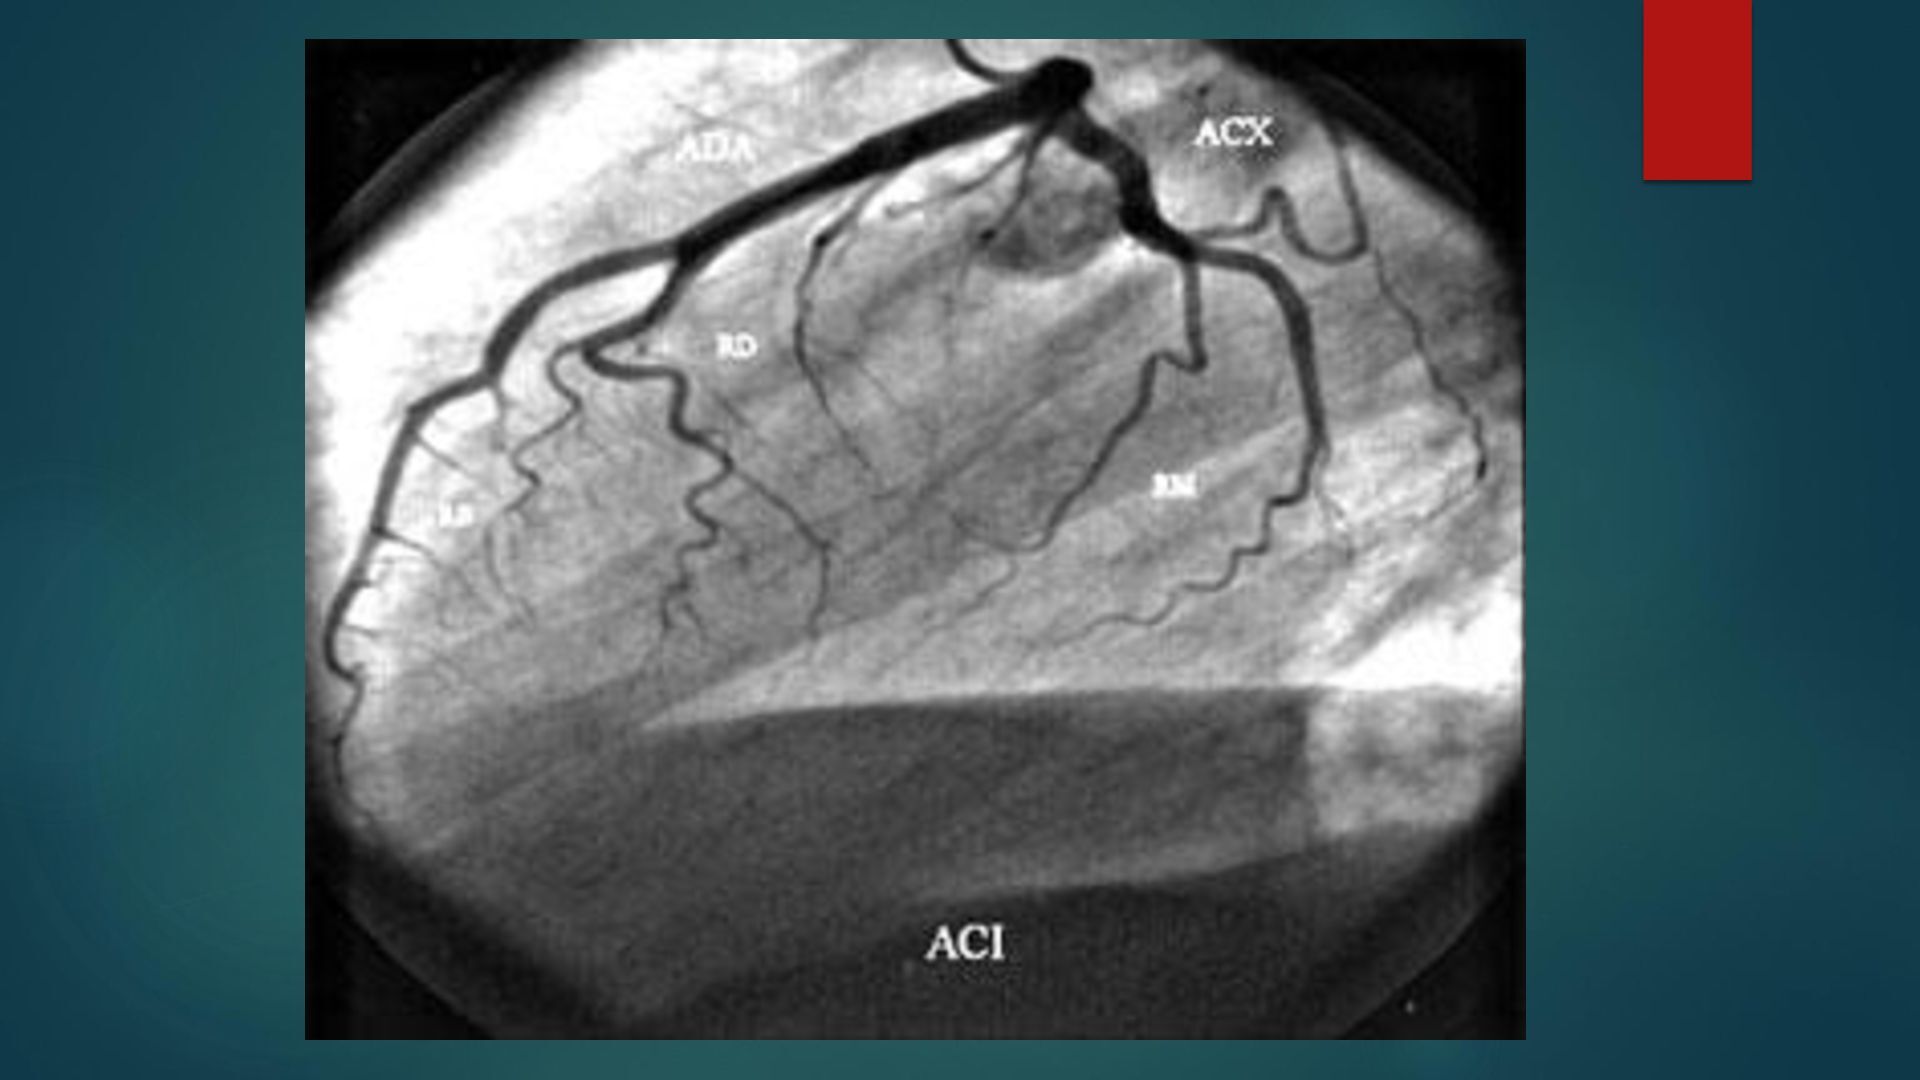

o g a c a r d i o v a s c u l a r ANATOMÍA Y FISIOLOGÍA CARDIOVASCULAR D r a . I s a m a r G . C h a v a r r i a B e r n a r d i n o